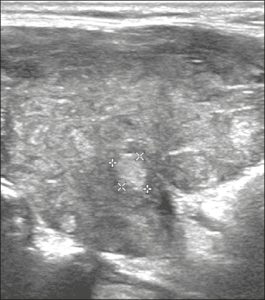

Hình 18. Hình ảnh nhân giáp dạng đặc (2 điểm), đồng âm (1 điểm), rộng hơn cao (0 điểm), có bờ trơn láng (0 điểm) và không có các ổ tăng âm hay bóng lưng (0 điểm). Do đó, tổng điểm là 3 điểm và mức độ nguy cơ được phân loại là TR3.